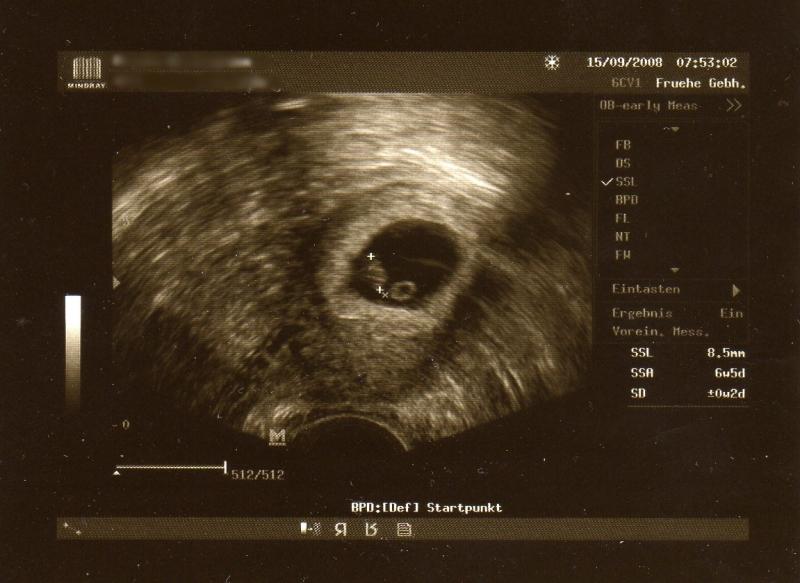

Ich war heute morgen nochmal zum Photoshooting - das Distelchen ist seit Mittwoch von 4,1mm auf 8,5mm gewachsen *FREU* - wenn ihr wollt stell ich heute Abend das Bildchen rein?

na klar seht ihrs nachher - mein Mann scannts dann ein - ich bin da unbegabt

das neue Bildchen, bitte schön:

[ATTACH]4233[/ATTACH]

Ist das eingentlich normal, dass das Distelchen schon rum schwimmt?

post-16256-13845604863195.jpg

Oh, Analussia, das ist aber ein schönes Bild! :) Wie weit bist Du denn jetzt schon?

Bin übrigens heute 7+0 - also 8. Woche, boah hört sich das gut an...